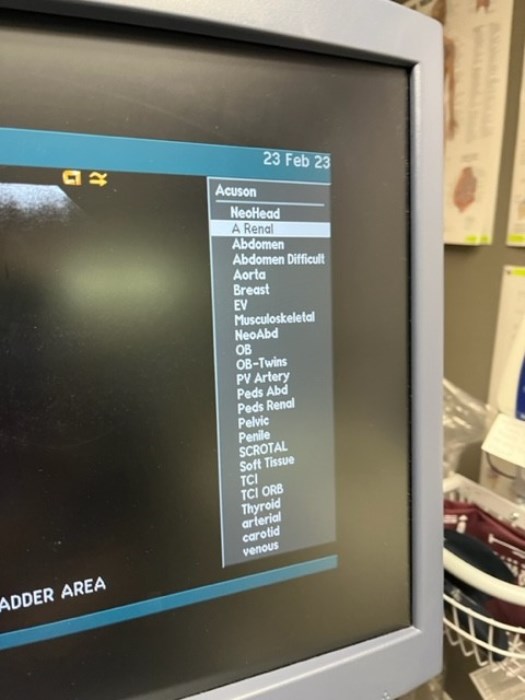

Siemens Sequioa Ultrasound

Pre-owned. In good working condition. Shown as is. Siemens Sequoia Ultrasound. DOM: 2006

Probes: 15L8w, 4V1, 10V4, 6L3, 4C1